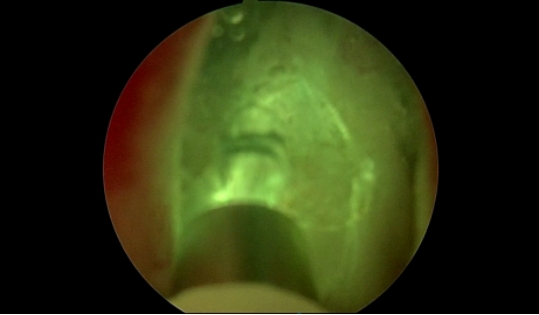

精准高效切除:在手术室团队的密切配合下,由范地兵副主任主刀带领手术团队,凭借丰富的经验和娴熟的操作,借助蓝激光电汽化技术精准地沿外科包膜层面,将增生的前列腺组织快速汽化吸出,通畅了尿道,从根源上解决了梗阻问题。术中视野清晰,几乎实现了“无血化”操作,极大地降低了手术风险。